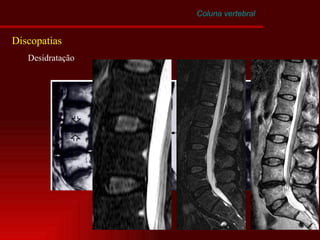

Coluna vertebral Discopatias Desidratação Herniação Anterior Intravertebral Posterior e postero-lateral

Desidratação Envelhecimento normal x Degeneração Discal Alterações macroscópicas anatômicas Alterações bioquímicas    Capacidade de ligação com a água Desintegração dos grandes proteoglicans moleculares    Conteúdo de Colágeno Coluna vertebral Discopatias

Coluna vertebral Discopatias Desidratação